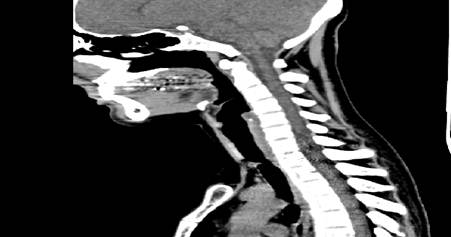

Tomografía axial computarizada: donde se constata una estenosis traqueal severa a nivel del cuerpo vertebral D-l (Fig.1 y Fig.2).

Traqueoscopia: donde se precisó la estenosis de más de un 50 % de la luz de la tráquea, a 20 centímetros de la arcada dentaria superior.